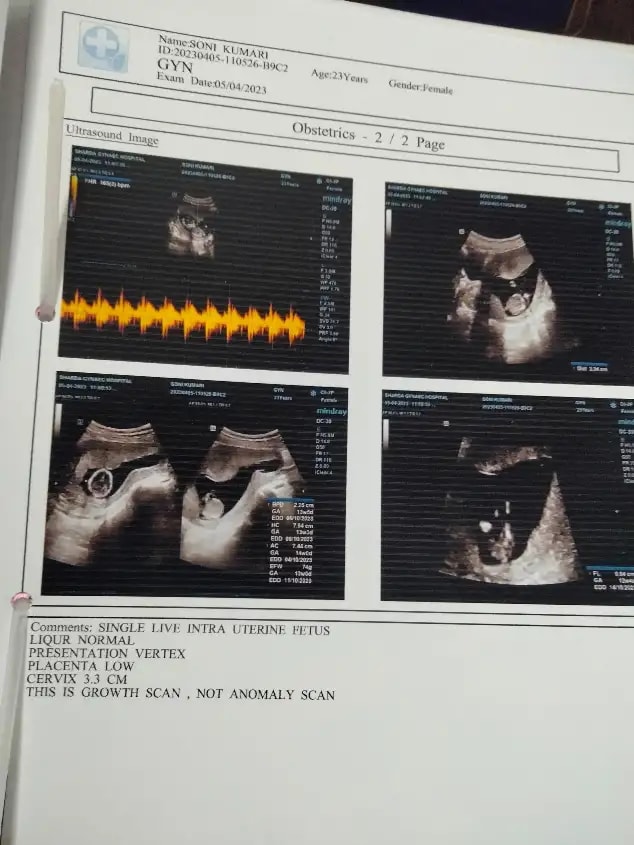

Q: Nt scan kya hota h mujhe to bs yahi report diya h sonography ka plz koi btaye nt scan ka matalab

• Hello sisters please meri ultrasound report dekhkar bataiye ki sab Kuch hai .... our meri pregnancy ko kitne din ho gay me bahut confused Hu ....mere hisaab se 7th month abhi start hua hai doctor ne Bola hai ki 7 month complete hone wala hai ..... please help me